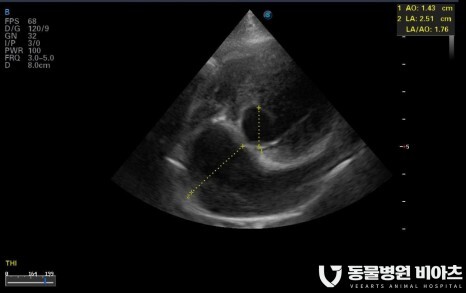

4. 엑스레이/초음파

초음파(LA:Ao, LVIDDN)

심장 초음파

심장 초음파는

심장 내강의 크기

심장벽 두께(LA:AO),

판막 모양의 이상 여부

혈관의 비정상적 확장 여부 등

엑스레이로는 확인이 어려운

심장 구조 변화의 많은 부분을 확인할 수 있습니다.